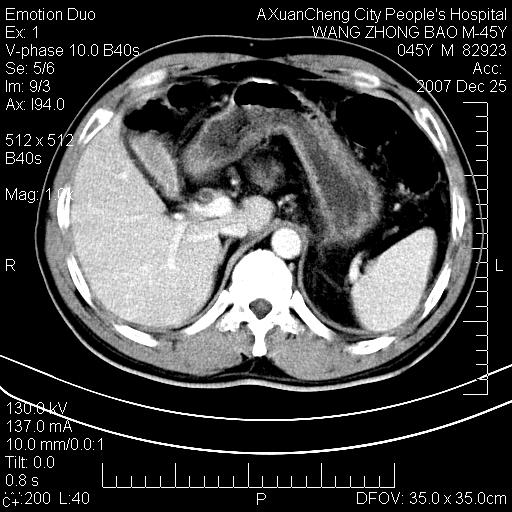

以下是引用qiuleiyu在2007-12-25 18:14:00的发言:[br]胰腺增大,周边渗出改变,肾前筋膜明显增厚,示少量积液.胆囊壁毛糙,周边少许渗出,胆总管壁厚,异常强化,然扩张不明显.结合病程急短;考虑;胆管炎,胆囊炎,胆源性胰腺炎可能大,请结合实验室检查及随访.

以下是引用lisihao在2007-12-25 14:23:00的发言:[br]急性水肿型胰腺炎[br]依据:1、胰腺弥漫性肿大,边缘稍毛糙;[br] 2、双侧肾周筋膜增厚,尤以左侧为甚(重要征象)[br] 3、双侧后胸膜增厚(刺激性炎症);[br] 4、结合病史,查血尿淀粉酶应该可以确诊。